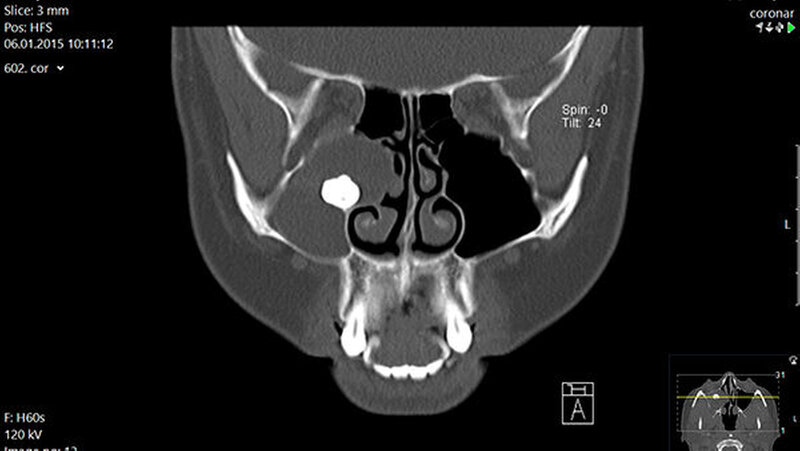

Röntgen (OPG Abb.1): verschattete Kieferhöhle rechts mit extrem verlagertem Zahn 18 direkt infraorbital

In der regionalen Klinik (Winterberg-Krankenhaus Saarbrücken) wurde zusätzlich eine kontrastmittelunterstützte Computertomografie der Nasennebenhöhlen durchgeführt (Abbildungen 2 und 3), die den Befund bestätigte und präzisierte.